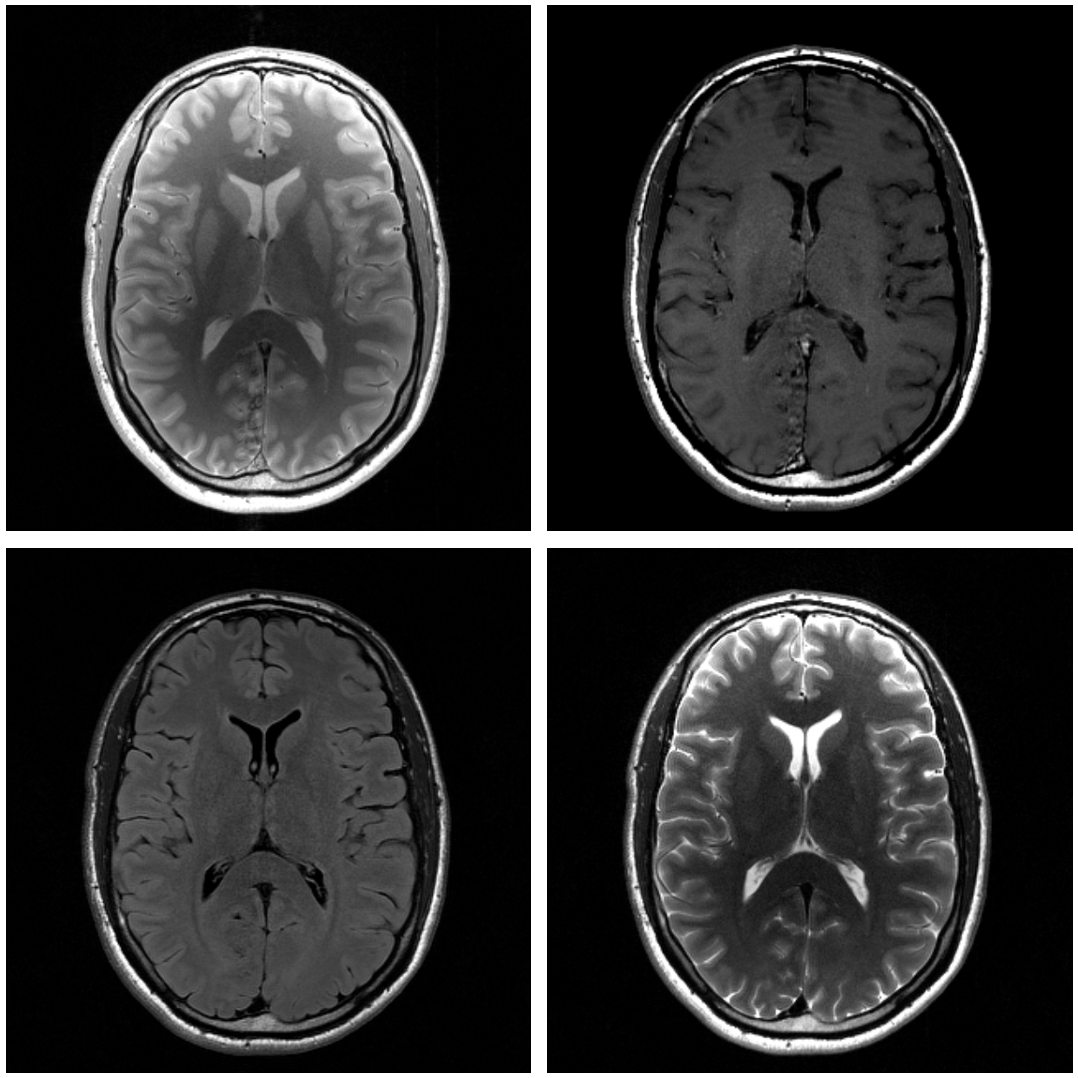

Refer to caption

Figure 1: Example of a single brain slice with four different contrasts. Proton Density (Top Left), T1 (Top Right), T2-Flair(Bottom Left), T2 (Bottom Right).